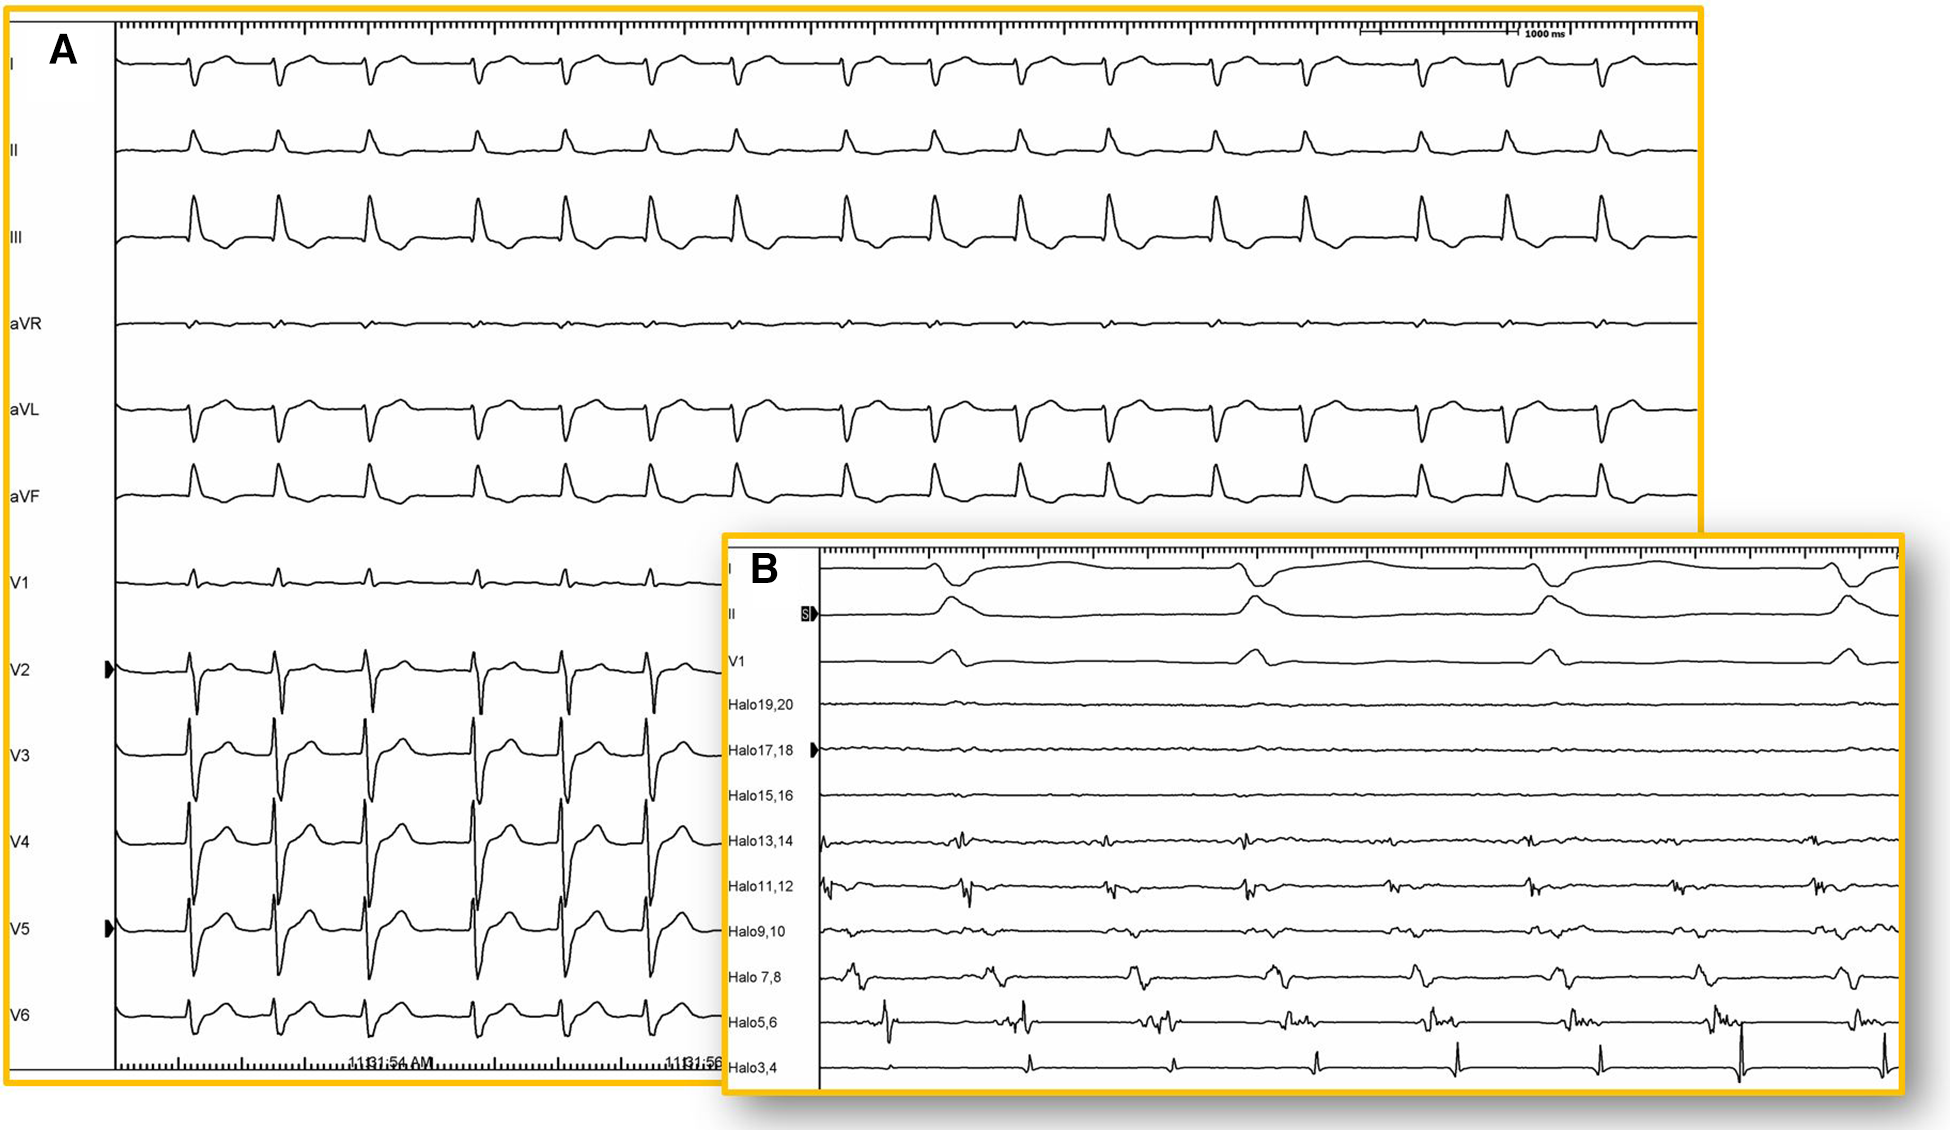

Figure 5

12-lead ECG. (A) Twelve-lead electrocardiogram (25 mm/s) of a patient with corrected d-TGA using the Senning technique. Atrial activity is very difficult to visualize due to its low amplitude and may be interpreted as atrial fibrillation. However, in the intracavitary recording (B) of the same patient, atrial activity is shown recorded by a duodecapolar catheter positioned between the superior and inferior vena cava (100 mm/s), revealing organized and regular activity. Electroanatomical mapping confirmed the presence of typical atrial flutter with a circuit around the tricuspid annulus (isthmus-dependent).